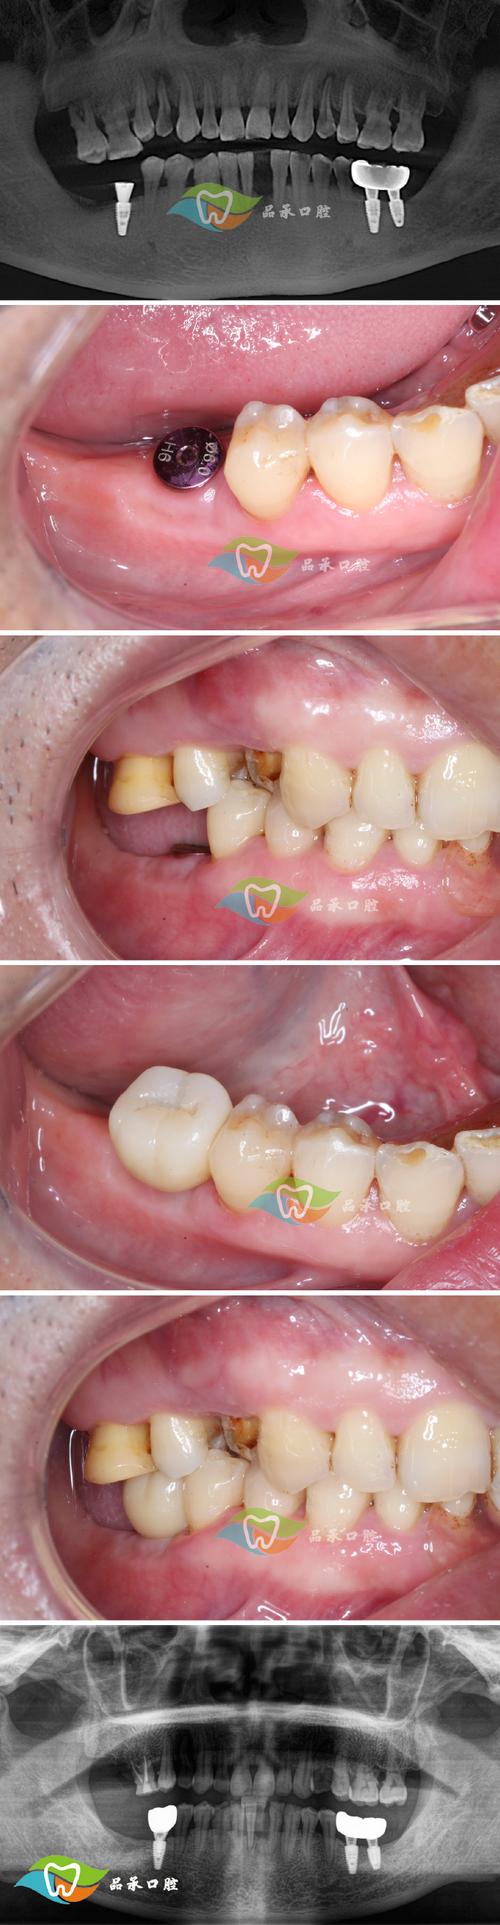

术后1个月、3个月、6个月是关键复查节点,通过临床检查和影像学评估(如X光片)确认种植体与牙槽骨的骨结合情况,骨结合通常需要3-6个月,若骨结合良好(种植体无松动、周围骨密度稳定),则可进入永久修复阶段;若骨结合不佳(如骨吸收明显、种植体松动),则需及时干预,可能需要进行植骨或调整治疗方案,以下为术后不同时间段的复查重点及护理要点: